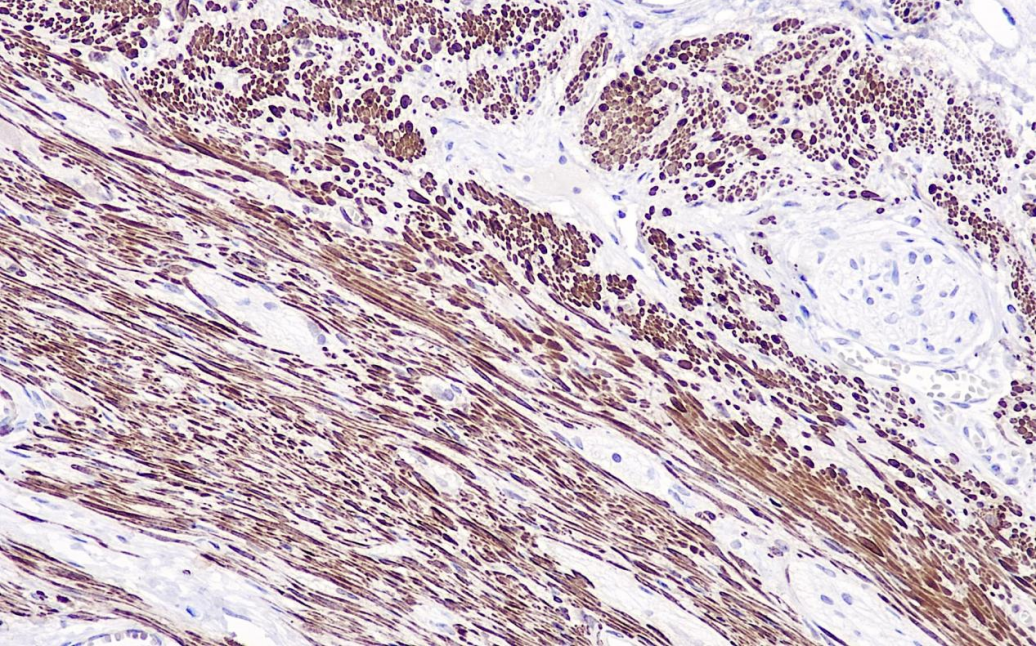

Calponin-1 is an actin-binding, pro-myosin calmodulin protein with a molecular weight of 34 kDa, which is a specific protein of smooth muscle cells and has the function of regulating the contraction of smooth muscle.Calponin-1 labels the myoepithelial cells in smooth muscle tissues as well as in the case of mammary lesions, and can be used for the study of the distribution of myoepithelial cells in smooth muscle tumors and mammary lesions.

Calponin-1 Antibody Reagent binds specifically to the Calponin-1 molecular antigen. Immunohistochemistry kits containing Calponin-1 Antibody Reagent are indicated for the precise diagnosis of smooth muscle tumors, smooth muscle sarcomas, and myofibroblastic proliferative lesions.